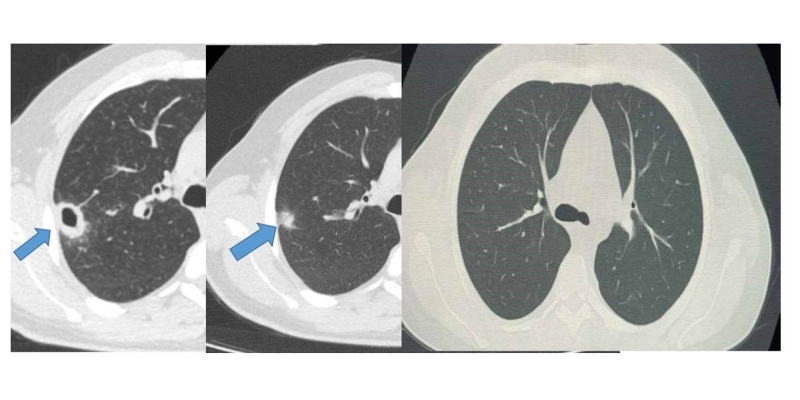

Bayburt Devlet Hastanesine öksürük ve balgam şikayetiyle başvuran 50 yaşındaki hastanın akciğerinde kitle benzeri bir doku tespit edildi. Yapılan tetkikler sonucu ciddi bir hastalık olmadığı belirlenen hasta, erken tanı ve doğru tedavi sayesinde sağlığına kavuştu.

Göğüs Hastalıkları Uzmanı Uzm. Dr. Hilal Sayma tarafından muayene edilen hastaya ileri tetkik amacıyla bronkoskopi işlemi uygulandı. Bronkoskopi sonucunda lezyonun kanser veya tüberküloz gibi ciddi hastalıklarla ilişkili olmadığı belirlenerek, hasta için uygun tedaviye başlandı.

İki haftalık tedavi sürecinin sonunda yapılan kontrollerde lezyonun neredeyse tamamen gerilediği görüldü. Sağlığına kavuşan hastanın taburcu edildiği ve durumunun iyi olduğu öğrenildi.